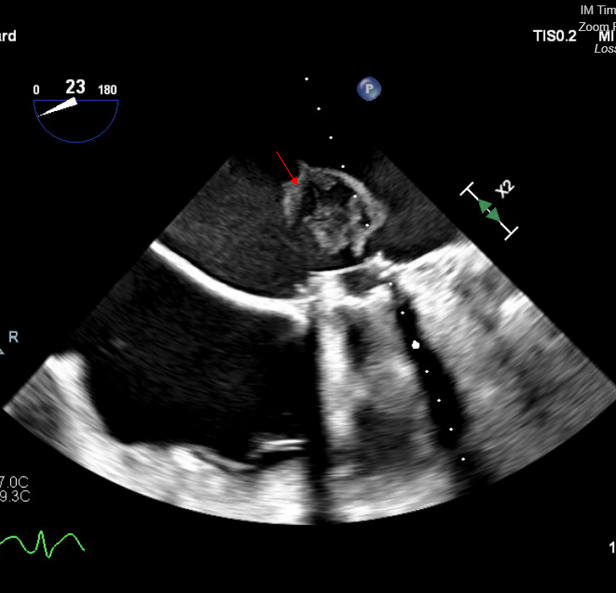

In order to prevent coronary or brain embolization of LAA thrombus, the decision was made to proceed with LAA ligation via the left thoracotomy approach. The patient was then subsequently taken to the operating room for clipping of the LAA with possible cardiopulmonary bypass only if necessary. The LAA was clipped through a left anterior thoracotomy. The patient already had access in her femoral artery and vein for possible institution of cardiopulmonary bypass should it be necessary. A large strand of thrombus was dislodged from the LAA and migrated in the left atrium, obstructing the mechanical mitral valve (Figure 2A-C). The patient was heparinized and placed on cardiopulmonary bypass.

We performed transseptal puncture using Versacross wire (Baylis Medical) and Baylis catheter, followed by septostomy using a 14 mm Armada balloon (Abbott) (Figure 3). We then advanced the AlphaVac system (Angiodynamics) to the left atrial and directed the tip of the funnel towards the thrombus (Figure 4), which was successfully removed after multiple runs of aspiration using the AlphaVac system. (Figure 5A, B). The system was then removed, and the femoral venous access was closed using Perclose (Abbott). The patient was transferred to the cardiothoracic intensive care unit for further monitoring. Unfortunately, after transfer, a stroke occurred in the patient’s right middle cerebral artery. Her goals of care were discussed with the family, and she was transitioned to comfort care. She died 3 days post-procedure.